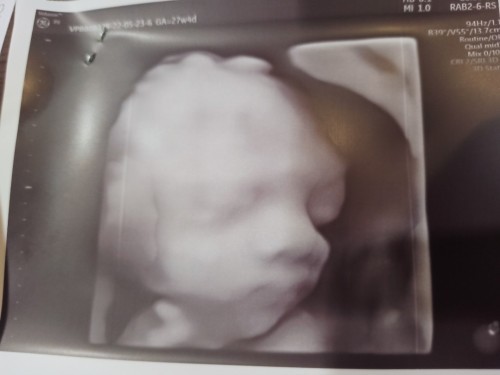

3 มิติค่ะแม่